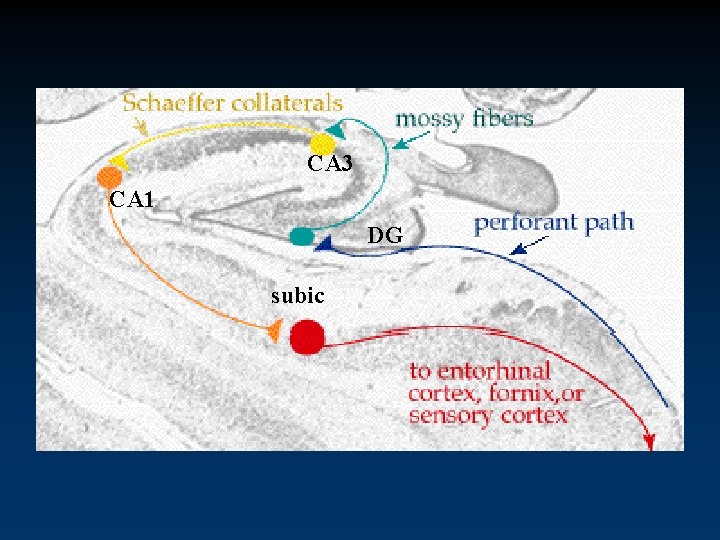

Integrated Circuitry Linking Temporal, Diencephalic, and Basal Forebrain Regions

CA 3 CA 1 DG subic